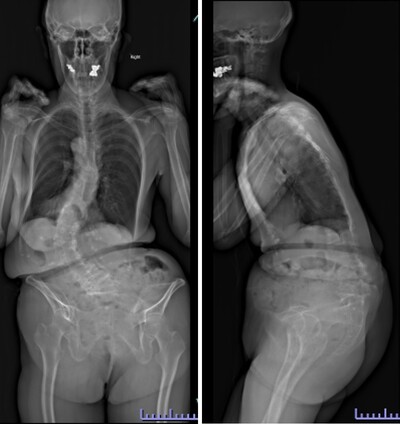

変性後側弯症で正面・側面ともに体幹バランスが破綻しています。まず腰椎側方進入前方固定術を行い、ある程度の矯正、土台を形成。1週間後に胸腰仙椎後方矯正固定術を行いました。正面・側面ともにバランスが良好に維持され、難治性の腰痛が改善しました。

典型的な変性後側弯症、成人脊柱変形の症例です。正面、側面いずれもバランスが破綻していて、立位持続・歩行が困難な状態です。

腰椎側方経路椎体間固定術と後方矯正固定術を2回に分けて行い、正面・側面ともに生理的なshapeが獲得されています。重要なことは、近年この生理的なshapeを取り戻すことが腰痛・歩行障害など患者さんの愁訴の改善に直結することが分かっていることです。

典型的な思春期特発性側弯症遺残変形・進行に伴う変性後側弯症・成人脊柱変形の患者さんです。正面・側面のバランスは破綻していて、難治性腰痛・脊柱管狭窄由来の下肢神経痛のためほぼ寝たきりとなっていました。

通常通り侵襲を軽減する目的で腰椎側方経路椎体間固定術、後方矯正固定術を2回に分けて行いました。正面・側面のバランスは良好で生理的な腰仙椎・体幹のshapeが獲得されています。腰痛、下肢神経痛は皆無となり、適度の散歩など穏やかな日常生活がおくれるようになりました。

高度腰曲がり・脊柱後弯症・成人脊柱変形の患者さんです。難治性の腰痛、バランス不良により歩くことも困難な状態でした。

腰椎側方経路椎体間固定術と後方矯正固定術を2回に分けて行い、生理的な胸椎後弯・腰仙椎前弯・骨盤前傾が復元されました。腰痛・歩行障害は改善し、近所のスーパーへ歩いて買い物にも行けるようになり、台所の仕事も痛みなく出来るようになりました。